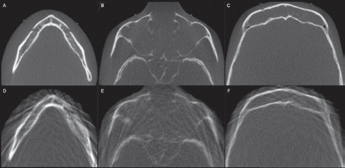

Es ist allgemein bekannt, dass bei der Akquisition einer digitalen Volumentomographie (DVT) mit Artefakten wie Aufhärtungen und Abschwächungen gerechnet werden muss. Obgleich die Rekonstruktionszeit erheblich reduziert wurde, die Auflösung der Aufnahmen immer höher wird und die Bildqualität ständig zunimmt, stellen Artefakte ein stets präsentes Problem in der Verfahrenskette dar. In manchen Fällen machen diese Artefakte gerade für den Ungeübten eine Bildanalyse unmöglich. In der Literatur werden Artefakte wie z. B. Auslöschungs- und Aufhärtungsartefakte beschrieben (Abb.6 u. 7). Sie sind technisch bedingt, während eine andere, sehr wichtige Ursache dieser Artefakte im Patienten selbst zu sehen ist. Da die Belichtung in der Regel mehr als ein paar Sekunden dauert und der Patient im Gegensatz zu der entwicklungsbezogenen These kein statisches Objekt darstellt, kann es passieren, dass er seinen Kopf während der Aufnahme bewegt. In diesem Fall findet man im rekonstruierten Datensatz sogenannte Bewegungsartefakte, die die Bildqualität erheblich beeinflussen können (Abb. 8).